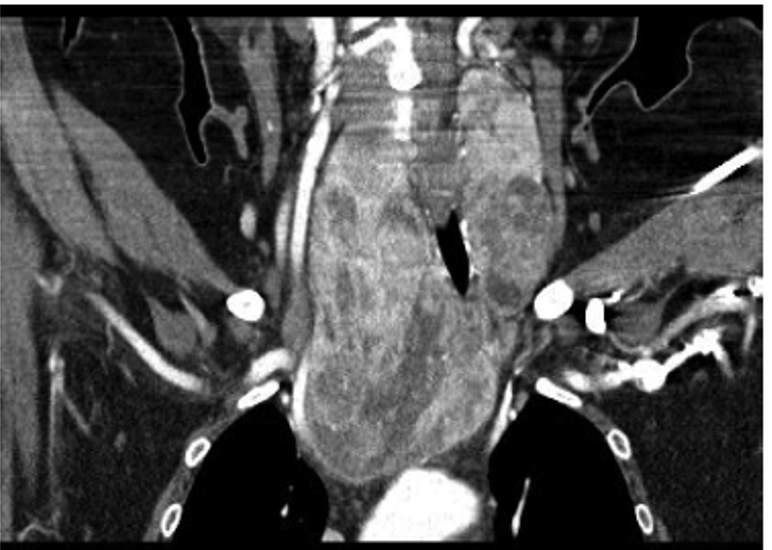

TC otro método de valoración que sirve para ver extensión de biocio hacia mediastino como en la imagen